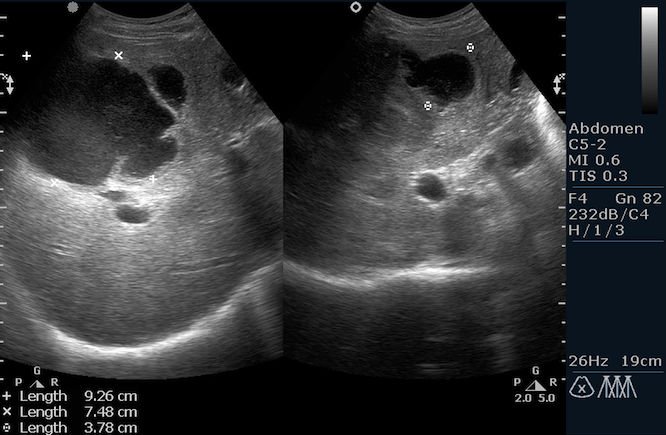

Снимок диагностического исследования при помощи ультразвука

УЗИ поясничного отдела

УЗИ поясничного отдела противопоказаний не имеет. Во время проведения процедуры пациент лежит на спине либо сидит. Врач в процессе исследования производит осмотр спинномозгового канала, спинномозговых нервов и межпозвонковых дисков. Исследование может проводиться двумя способами: посредством переднего доступа (датчик ультразвуковых волн помещается на животе) или с использованием заднего доступа через междужковые пространства (датчик прикладывается к спине в районе поясницы).

Что показывает УЗИ поясничного отдела?

Ультразвуковое исследование позвоночника – метод высокоинформативный. Проведение УЗИ поясничного отдела позволяет доктору четко визуализировать последствия родовых травм у детей, а также возрастные изменения у пациентов пожилого возраста. Данная процедура дает возможность точно поставить диагноз при подозрении на грыжи, позволяет увидеть очаги воспаления и определить степень разрушения межпозвонковых дисков.